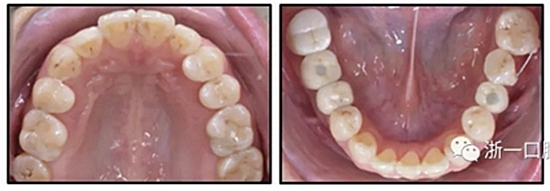

36歲;女性;尋求下頜左后方區(qū)域間隙管理的建議(圖1和圖2),通過治療獲得了良好的牙頜面效果(圖3和圖4)。她被診斷患有骨性I類和代償性牙性II類錯合畸形,并且上頜左側(cè)尖牙缺失(圖1和2)。大約七年前,由于不可修復(fù)的齲齒,拔除了下頜左側(cè)第一和第二磨牙(圖5)。37相鄰的第三磨牙向近中移動并傾斜入間隙,導致無牙頜間隙減小至約14 mm(圖2和圖5)。臨床和影像學評估顯示多發(fā)性齲損和在下頜右側(cè)567處有一不良的固定橋修復(fù)體(圖1和5)。此外,下頜左中切牙缺失,造成下頜中線向左側(cè)偏移約3 mm(圖1和圖2)?;颊咦栽V,她的右上第一前磨牙和左上尖牙在13歲時由其家庭牙醫(yī)拔除,因為它們被阻塞到頰側(cè)萌出(圖1)。上頜第二磨牙缺失(未知病因),并且相鄰的第三磨牙已經(jīng)轉(zhuǎn)移到第二磨牙間隙中。如補充材料所示,美國正畸學差異指數(shù)DI是28分。種植體部位(下頜左側(cè)和右側(cè)第一磨牙)由于復(fù)雜性得到額外4分(補充材料)。

圖1. 治療前面部和口內(nèi)照片